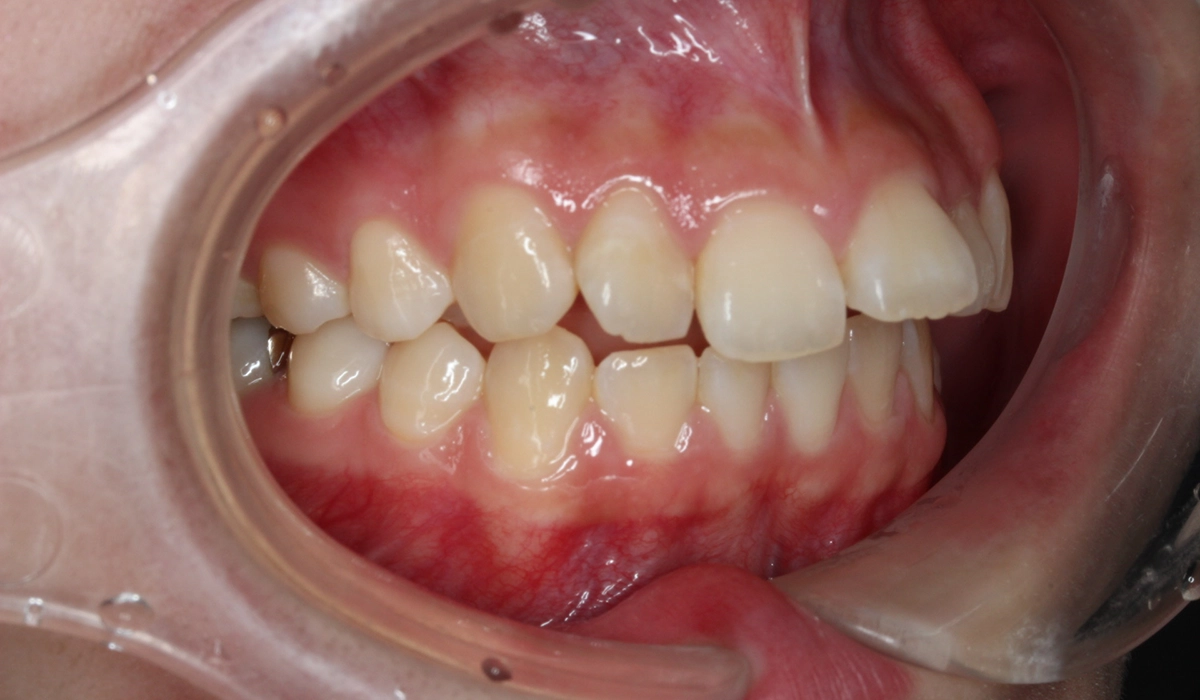

術前:右側

術後:右側